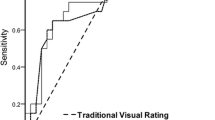

The diagnostic performance of the automatic system was comparable to that of visual inspection by experts. The area under the ROC curve for the automatic diagnosis system was 0.77. The mean area under the ROC curve for visual inspection by experts and beginners was 0.76 and 0.65, respectively.

We performed a receiver operating characteristic (ROC) analysis to compare the automatic system with visual reading. For ROC analysis of the fully automatic diagnosis system, the averaged Z scores in the prototype ROI map of each subject in the second group were used. The areas under the curves were calculated using ROCKIT software 0.9B (Dr. Metz, Department of Radiology, The University of Chicago).

The averaged Z scores in each area of the ROI map obtained in the second group are shown in Table 3. All the averaged Z scores in each region for DLB were significantly larger than those for AD. The fully automatic diagnosis system demonstrated an accuracy of 73%, a sensitivity of 75% and a specificity of 72% for the mild DLB group when the threshold was set at the mean+2SD. When using the threshold of the mean+3SD, an accuracy of 61%, a sensitivity of 38% and a specificity of 76% were demonstrated.

Figure 2 shows each observer’s area under the ROC curve (Az) for visual inspection of conventional FDG-PET images (Az = 0.83–0.58) and for the fully automatic diagnosis system (Az = 0.77), using the threshold of mean+2SD. There was no significant difference in the area under the ROC curve between the automatic diagnosis system and the visual inspections. The diagnostic value of the automatic system was compared with that of the observers (Table 4).

As shown in our study, although visual inspection by the readers provided good diagnostic accuracy, the area under the ROC curve was not as large as we had expected (mean Az = 0.7145). It can be difficult to make a diagnosis of mild DLB because occipital glucose metabolism is not always decreased more severely in mild DLB than in mild AD. The difference in the metabolic reduction between mild DLB and AD was smaller than we had anticipated, and this may be the reason why even experts had difficulty in diagnosing some of the mild DLB cases in this study. The area under the ROC curve was accordingly small, and the same results were obtained using our automatic diagnosis system. It is also to be borne in mind that while DLB accounts for about 20% of dementia cases, in the sample in this study the percentage was 40%. Since DLB patients also show the patterns of AD on FDG-PET images, this high prevalence of DLB may have led to underestimation of the diagnostic performance of the readers and of the automatic method as well. While our diagnostic system performed similarly to the experts in diagnosing mild DLB, the ROC curve of the automatic system was shifted slightly to the right; this indicates that the diagnostic performance in respect of AD patients varied more widely than that in respect of DLB patients (i.e. there were fewer misdiagnoses in DLB patients), and in clinical use this system might have the advantage of having a high sensitivity for identification of early DLB.